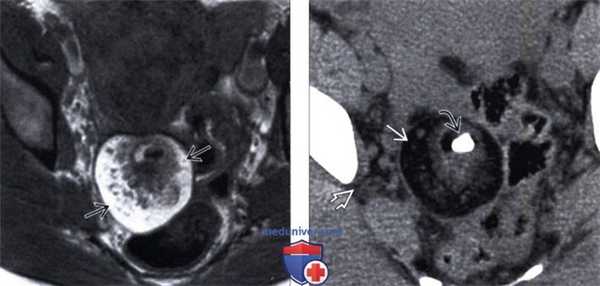

(Слева) На МРТ Т1 дермоид имеет гиперинтенсивный внутренний сигнал, который представляет собой скопление жира.

(Справа) КТ с контрастированием того же дермоида, аксиальный срез: определяется кальцинированный зуб, который обнаруживается в 1/3 случаев. Обратите внимание, что жир в дермоиде заметно гиподенсивнее по сравнению с внебрюшинным жиром.

5. МРТ при тератоме яичника:

• Т1-ВИ:

о Гиперинтенсивные компоненты = жир

• Т1-ВИ, режим подавления сигнала от жира:

о При подавлении сигнала от жира, утрата высокой интенсивности сигнала на Т1 позволяет отличить жир от продуктов крови:

- ↓ интенсивности сигнала = жир внутри тератомы

• Т2-ВИ:

о Различная интенсивность сигнала от жирового компонента может быть ошибочно принята за продукты крови